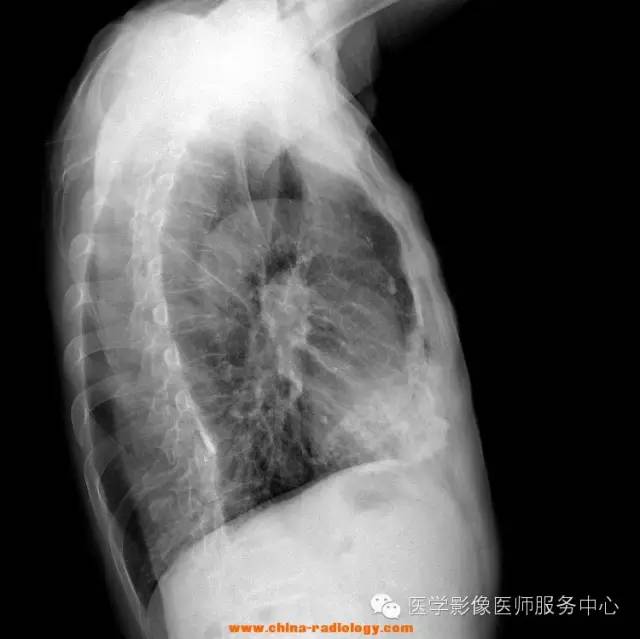

79Y,M,20160420。间断性咳嗽、胸闷多年。

透视下转位,切线位下,见侧胸壁上片状钙化影,并不随肺呼吸而运动。